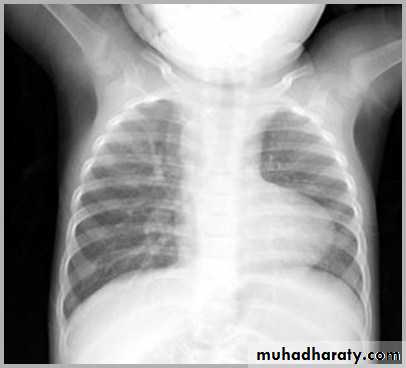

Normal thymus gland ( sail shape sign )